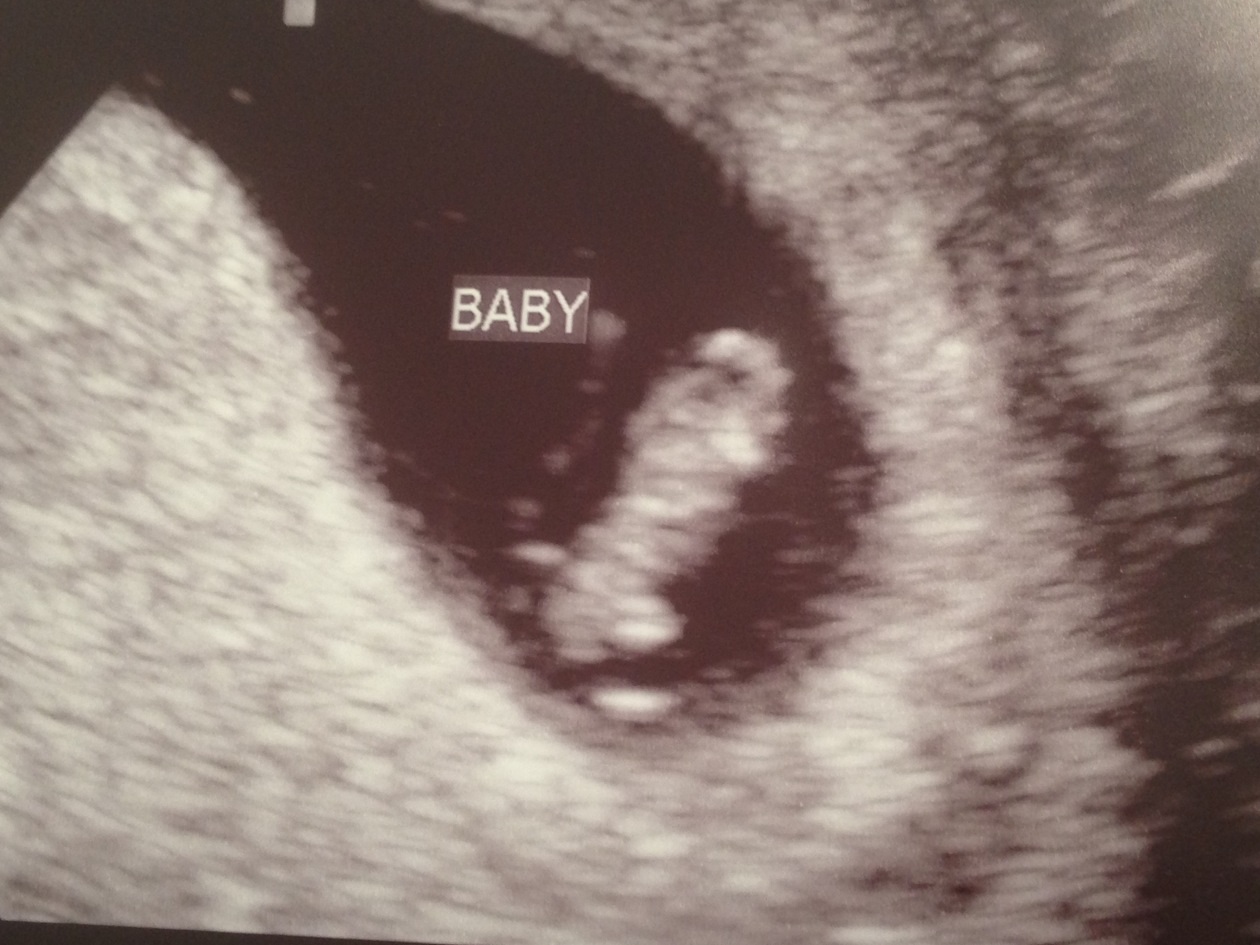

First u/s! Happy pGal mama! PIP

Baby was measuring right on track with a heartbeat of 150bpm. I was so nervous going in but am thrilled to finally feel like I can get excited about this one!! Yay!

• Great news! Am I right that you can see eyes on the pic on the right? :)

• LoL, I thought so too but it is actually brain! But you can see little legs forming.